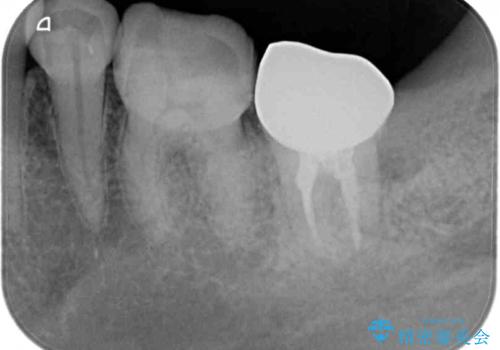

仮歯が途中外れることもなく、無事に補綴治療を行うことができました。

歯石や磨き残しなどが多いため、今後クリーニングを行っていきます。